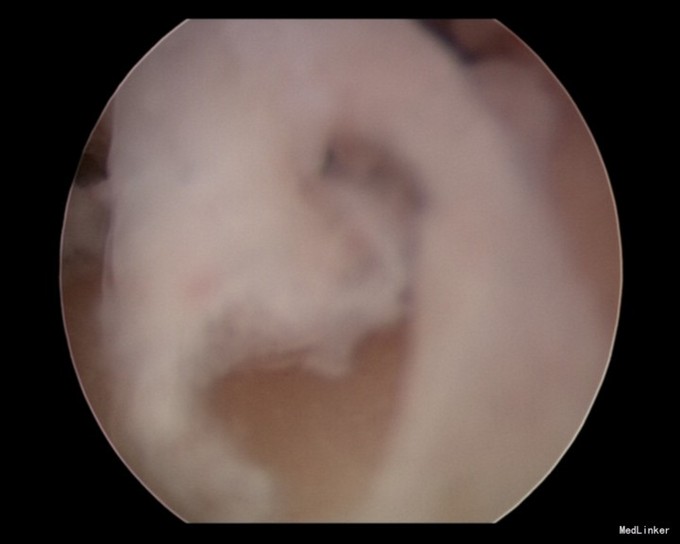

查体:全身查体及妇科查体未见异常。 辅助检查: 妇科超声:宫腔线不连续,考虑宫腔粘连可能性大。 宫腔镜检查:宫腔形态异常,如桶状,偏小,中间可见肌性粘连。

诊断:宫腔粘连 治疗:完善相关检查后2015-12-3于我院行宫腔镜检查术+宫腔镜下粘连电切术,术后放置宫内节育器及球囊防止粘连,给以人工周期三月治疗。

术后三月复查宫腔镜,未见明显粘连,于生殖中心移植胚胎。 宫腔粘连是一种人流术后常见并发症,严重影响患者生育功能及月经情况,建议广大妇女做好避孕措施。